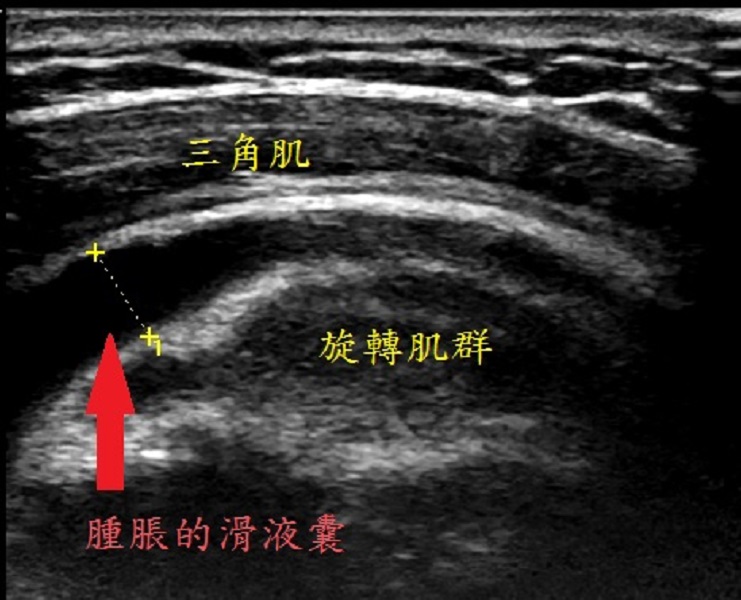

▲在超音波底下可以看到三角肌下滑液囊腫脹變大,進行滑液囊積液抽吸並施行注射治療。(圖/朴子醫院提供) 羅嘉元醫師表示,滑液囊是一種封閉性的囊袋狀結構,其內部充滿少量的黏滑液,多存在肌腱之間,或肌肉行經骨骼突起的位置,具有幫助關節運動與使活動平順的功能。滑囊引起發炎的原因,可能是反覆性的活動造成的壓迫,與摩擦而引起發炎反應,也有可能是外傷所造成發炎現象,其他較少見的原因可能是自體免疫疾病或感染造成。

羅嘉元醫師指出,治療三角肌下滑液囊炎的方法,包括避免反覆手臂高舉過肩的動作、口服非類固醇消炎止痛藥緩解發炎和腫脹所帶來的疼痛;物理治療方面,可以使用紅外線、雷射儀器治療,及經皮電刺激緩解疼痛。再不行就可安排肩部肌肉骨骼超音波檢查,在超音波底下可以看到三角肌下滑液囊腫脹變大,進行滑液囊積液抽吸並施行注射治療。